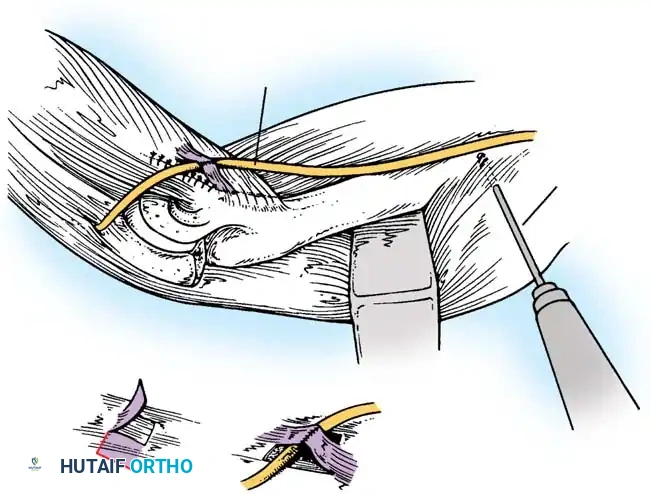

Ulnar Nerve Neurolysis

Before any deep dissection, locate the ulnar nerve proximally. Dissect it meticulously from its bed along the postcondylar groove of the medial epicondyle.

Careful isolation and vessel-loop control of the ulnar nerve are mandatory before addressing the medial joint capsule.

Triceps Flap and Subperiosteal Stripping

Beginning proximally, use sharp dissection to reflect the aponeurosis of the triceps distally, forming a robust tongue-like flap of tissue that remains attached to the olecranon.

Starting 7.5 cm proximal to the joint, make a midline incision through the underlying muscle fibers of the triceps down to the olecranon. Curve this deep incision around the lateral edge of the olecranon.

Fig. 58-26 Speed technique of open reduction. A, Incision and ulnar nerve isolation. B, Triceps aponeurosis reflected distally; subperiosteal stripping of muscles. C, Lateral view showing extent of mobilization. D, V-Y closure.

Subperiosteally free all muscle attachments from the distal humerus, both anteriorly and posteriorly.

Aggressive subperiosteal elevation is required to mobilize the distal humerus completely.

Release the attachments of the joint capsule and collateral ligaments around the humeral condyles. Mobilizing the tissues around the medial condyle and anterior humerus can be exceptionally difficult due to scarring, but complete mobilization of the distal humerus is non-negotiable for reduction.